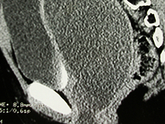

Cứu sống bệnh nhân 69 tuổi nhờ phẫu thuật khối u sau phúc mạc 20cm

Các bác sĩ Bệnh viện Hữu nghị Việt Đức vừa phẫu thuật thành công, cứu sống một nữ...